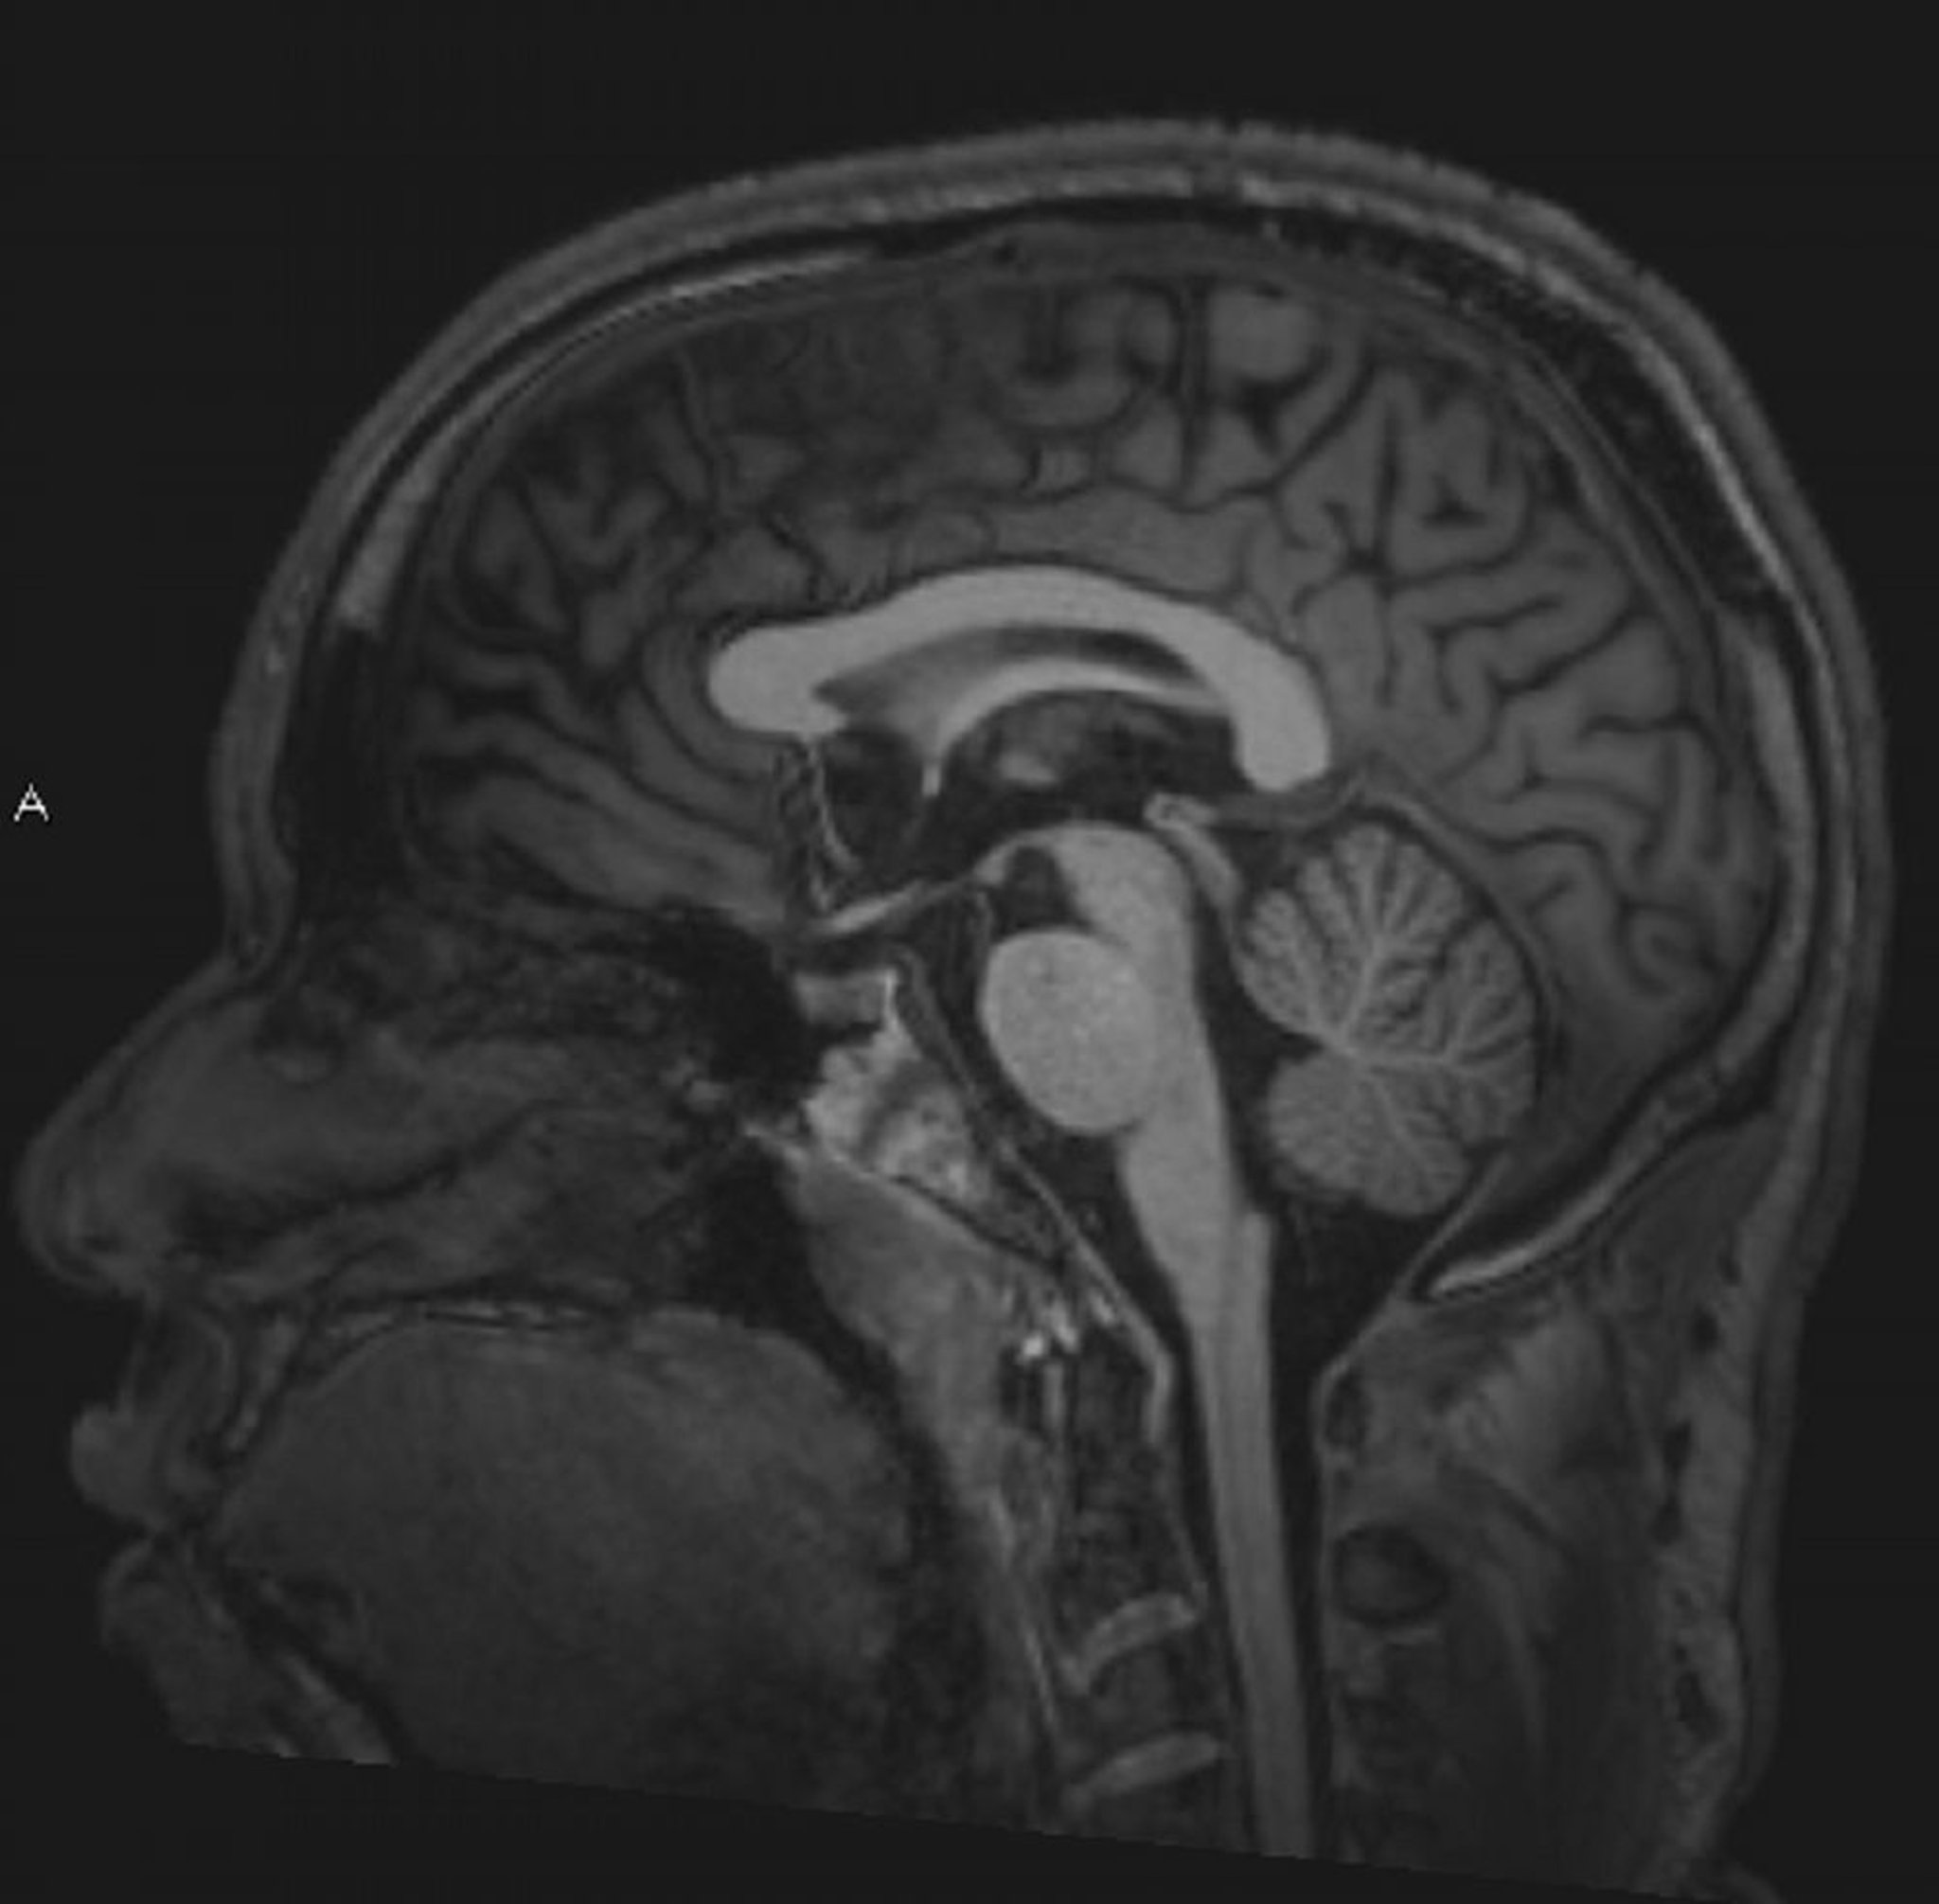

Normales MRT des Gehirns (sagittal) – Folie 4